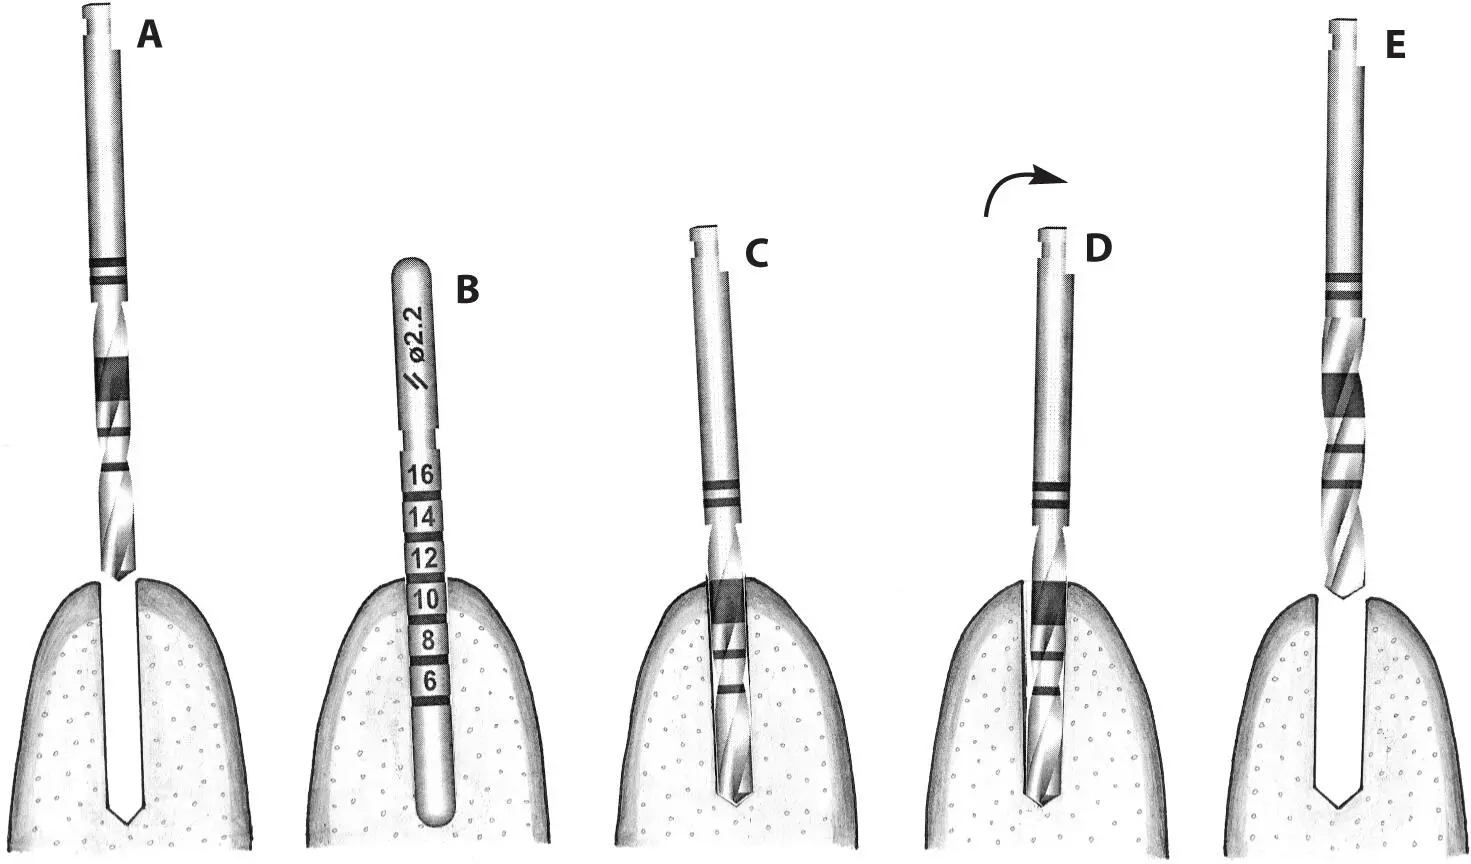

Fig 1-3d After the use of the first pilot drill (A) , a 2.2-mm-diameter guide pin is used to check the axis and depth of the implant preparation (B) . Any incorrect axis orientation can be adjusted with the same 2.2-mm-diameter pilot drill (C and D) and then followed with the 2.8-mm-diameter spiral drill (E) .